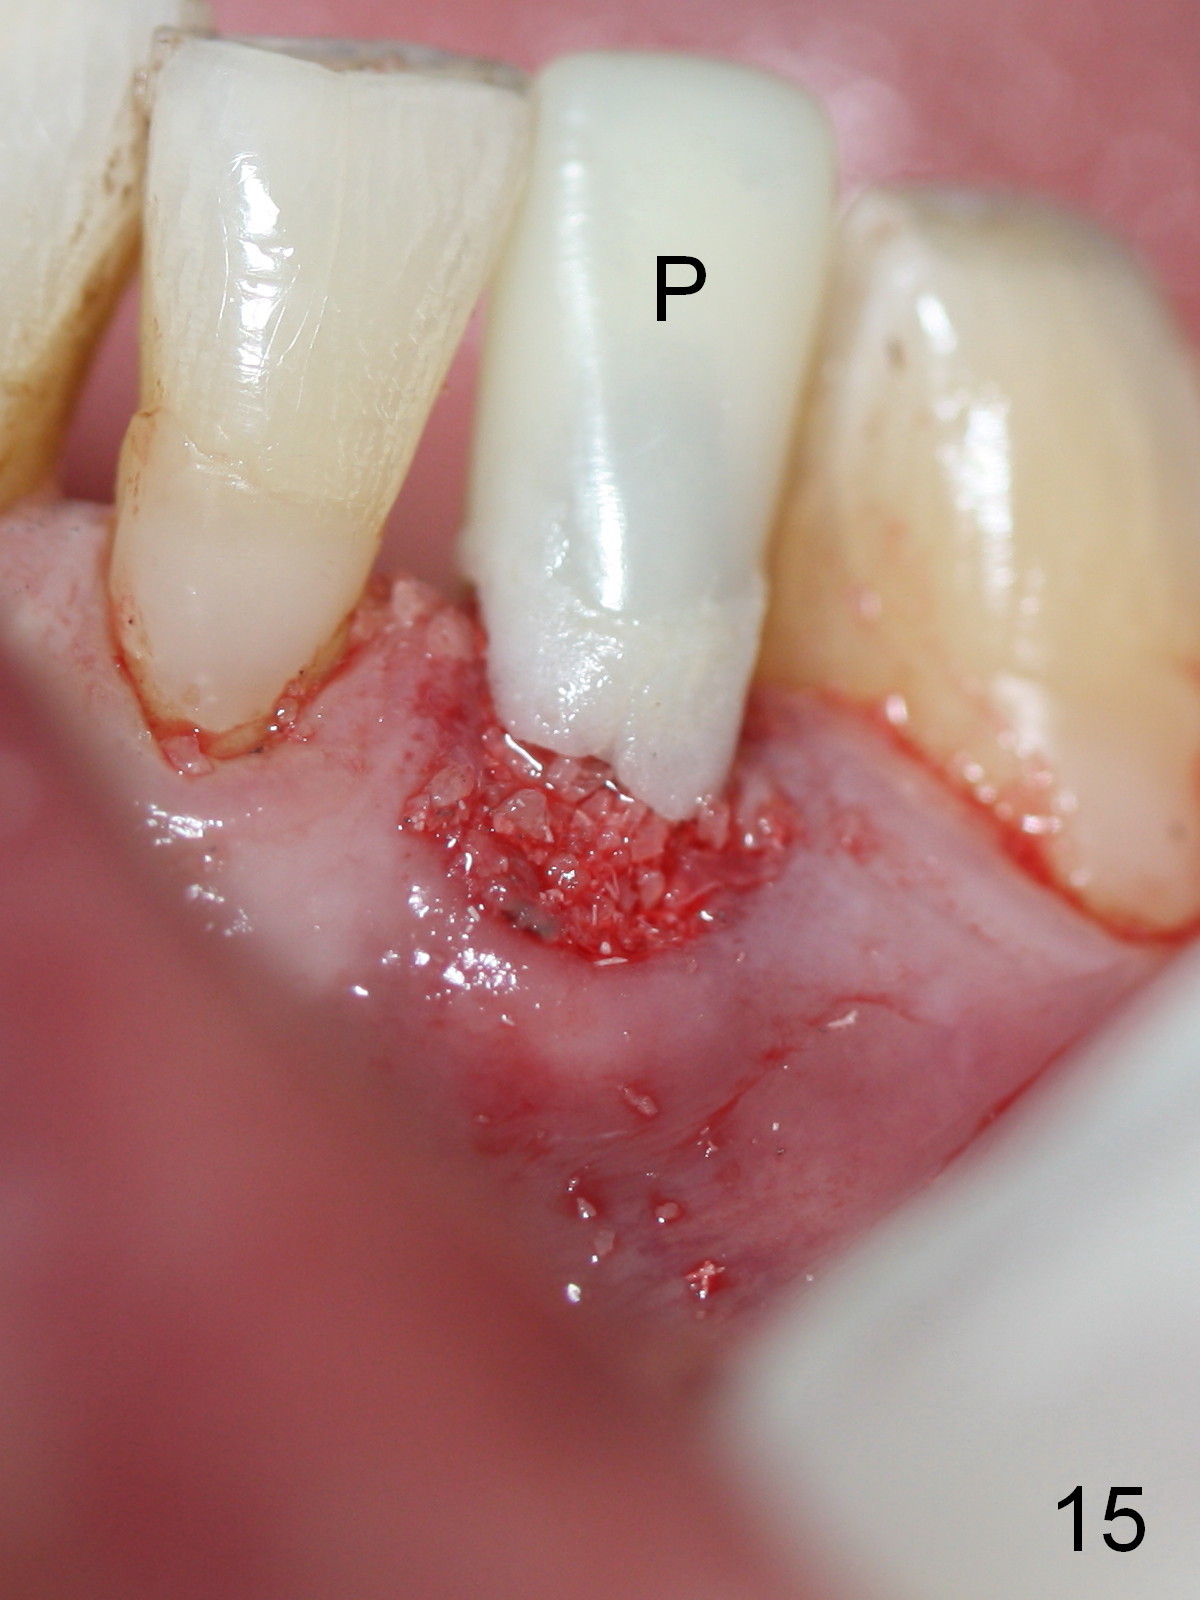

A 74-year-old man has several missing teeth (Fig.1). His 1st goal is to replace the lower left lateral incisor (Fig.2). The residual root has an apical lesion (Fig.3 *). To describe intraop findings, a CT image of a different patient is used (Fig.4 coronal section; B: buccal; L: lingual). After extraction, the buccal plate is found to be thin and low (Fig.5 arrowheads). A 1.5 mm pilot drill (Fig.6 red line) is used to initiate osteotomy in the lingual plate of the socket. Once the drill penetrates the lingual plate, the trajectory changes and the depth is 17 mm from the gingival margin (Fig.7). A PA is taken (Fig.8); it appears that the osteotomy can be extended more apically. When the pilot drill extends to 20 mm, there is sudden empty feeling. The lingual plate has perforated (Fig.9). A new osteotomy is established buccally (Fig.10 pink). To avoid buccal plate perforation, especially in the buccal undercut area (>), the coronal end of the drill has to be tilted buccally (<--). An angled abutment (3x20 mm, 15°) is placed (Fig.11,12). The abutment is modified (Fig.13,14) to accommodate an immediate provisional (Fig.15,16 P). Perio dressing is to be applied to prevent the bone graft from getting dislodged buccally (Fig.15). The dressing is in place 7 days postop (Fig.17).